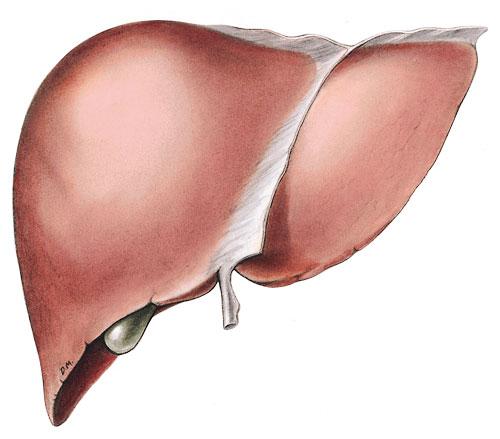

Liver